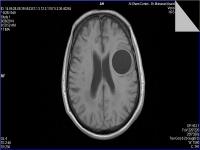

Medical imaging is an important investigative tool will help doctors to reach for the diagnosis of certain diseases, and the the advanced and high-quality imaging technologies are an important factor in maintaining the health of patients and accurate diagnosis of pathological lesions.